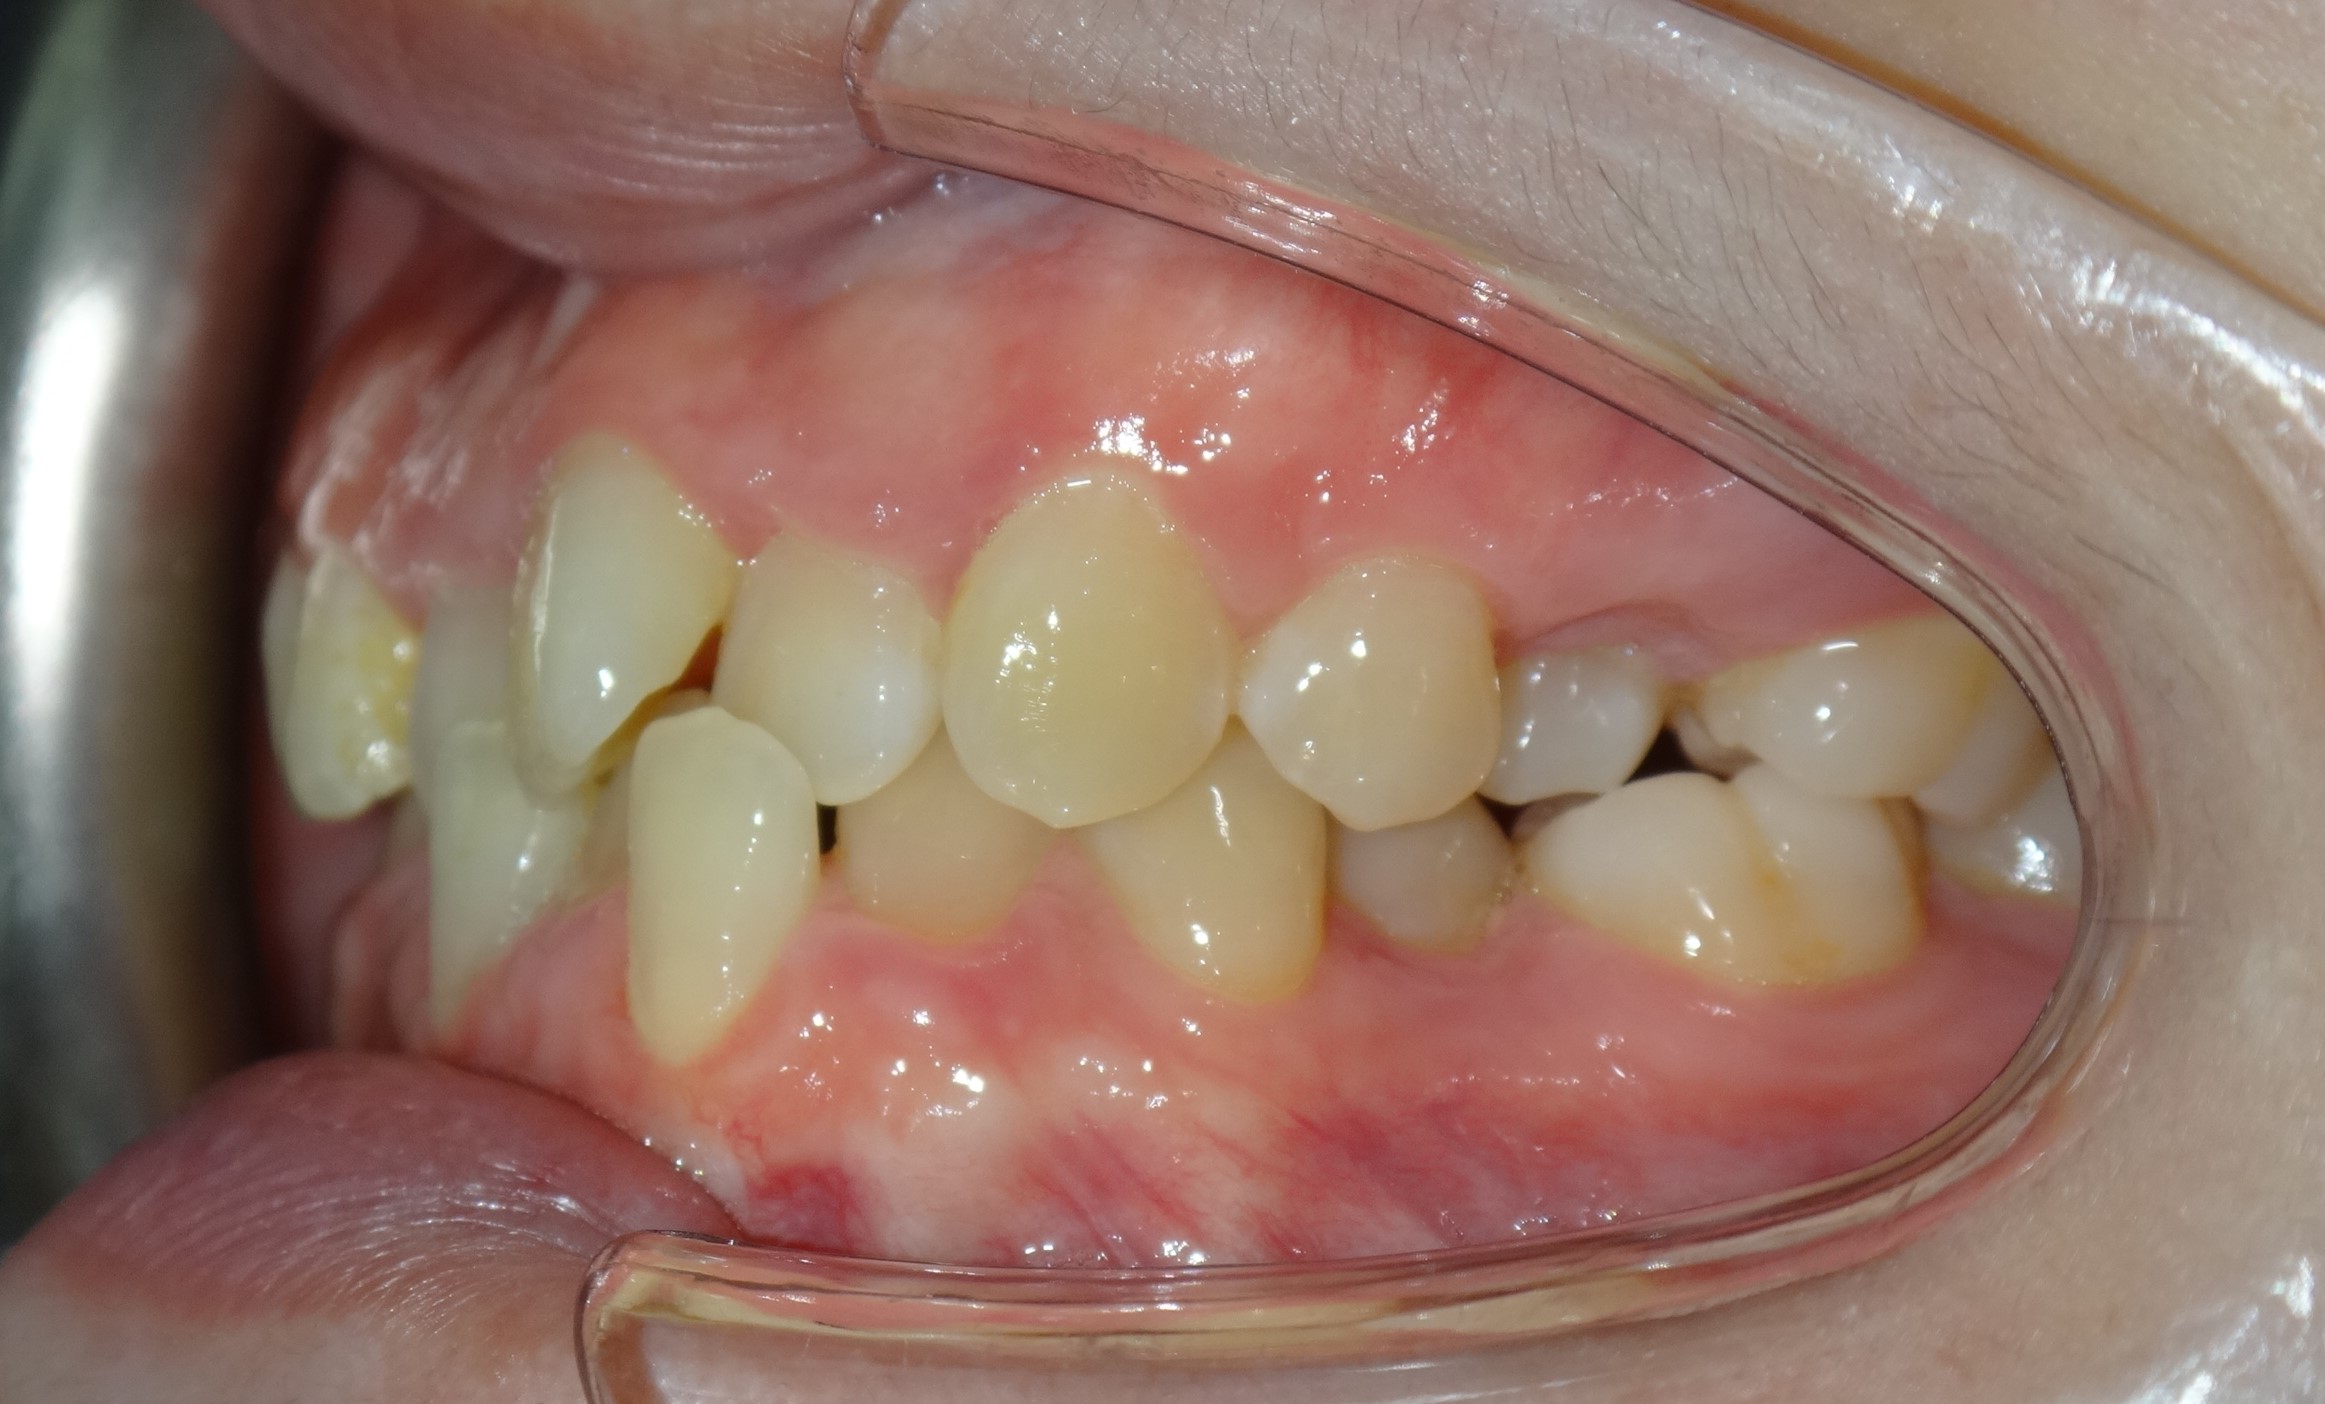

不拔牙案例 首頁 案例分享 齒顎矯正 不拔牙案例 - 矯正不拔牙案例 - 年紀:27歲 治療方式:隱適美隱形矯正 時間:34個月 主訴:前牙錯咬、排列不整 矯正前 矯正後 矯正前 矯正後 矯正前 矯正後 聲明:本所療程皆由專業醫生評估後,依照個人口腔狀況進行治療。因每位患者個別狀況不同,術後狀況也不盡相同,需親來本所由醫生評估。